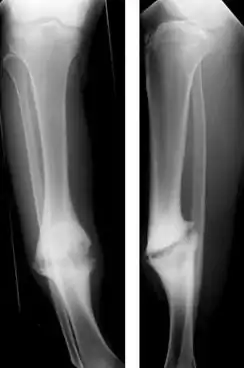

| Hypertrophic nonunion of the tibia | |

In a hypertrophic nonunion, the fracture site contains adequate blood supply but the fracture ends fail to heal together.[6] X-rays show abundant callus formation. This type of nonunion is thought to occur when the body has adequate biology, such as stem cells and blood supply, but inadequate stability, meaning the bone ends are moving too much. Typically, the treatment consists of increasing stability of the fracture site with surgical implants.[7]